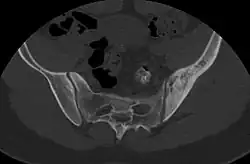

CT scan of primary B cell lymphoma in the left ilium, as diffuse cortical and trabecular thickening of the hemipelvis, mimicking Paget's disease.[2]